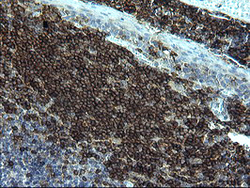

Supportive validation

- Submitted by

- OriGene (provider)

- Main image

- Experimental details

- Immunohistochemical staining of paraffin-embedded Human lymph node tissue within the normal limits using anti-CD22 mouse monoclonal antibody. (Heat-induced epitope retrieval by 10mM citric buffer, pH6.0, 120C for 3min, TA506405)

- Validation comment

- IHC